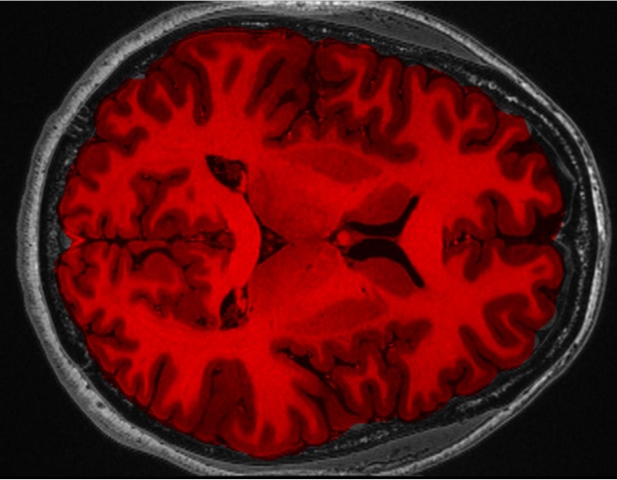

Для построения объемного изображения мозга требуется серия МРТ-снимков, которые в совокупности представляют собой трехмерную матрицу объемных пикселей — вокселей. Они отображают интенсивность реакций атомов водорода в организме на магнитное поле, из которой убираются шумы — воксели с очень низкой и очень высокой интенсивностями. В результате, по словам Александра Грищенко, получаются «чистые» данные сканирования головы.

Для построения изображения именно мозга необходимо выделить его из полученного массива данных. Как рассказал разработчик, алгоритм выделения головного мозга основывается на методе деформируемой поверхностной модели, когда в центр головы на МРТ-снимках помещается тесселированная сфера (сфера из огромного количества полигонов).

«Около каждой вершины полигонов, из которой состоит сфера, происходит сравнение интенсивностей, на основе чего принимается решение о том, будет модель мозга в этой точке «разрастаться» или «ужиматься». Алгоритм постоянно корректирует положение вершин, чтобы они располагались равномерно, без складок и разрывов. Это позволяет сохранить реалистичную и целостную форму мозга на протяжении всего процесса деформации. Эти действия повторяются многократно для достижения максимальной точности модели. Таким образом формируется контур мозга, по которому уже определяется его объем», — рассказал Александр Грищенко.